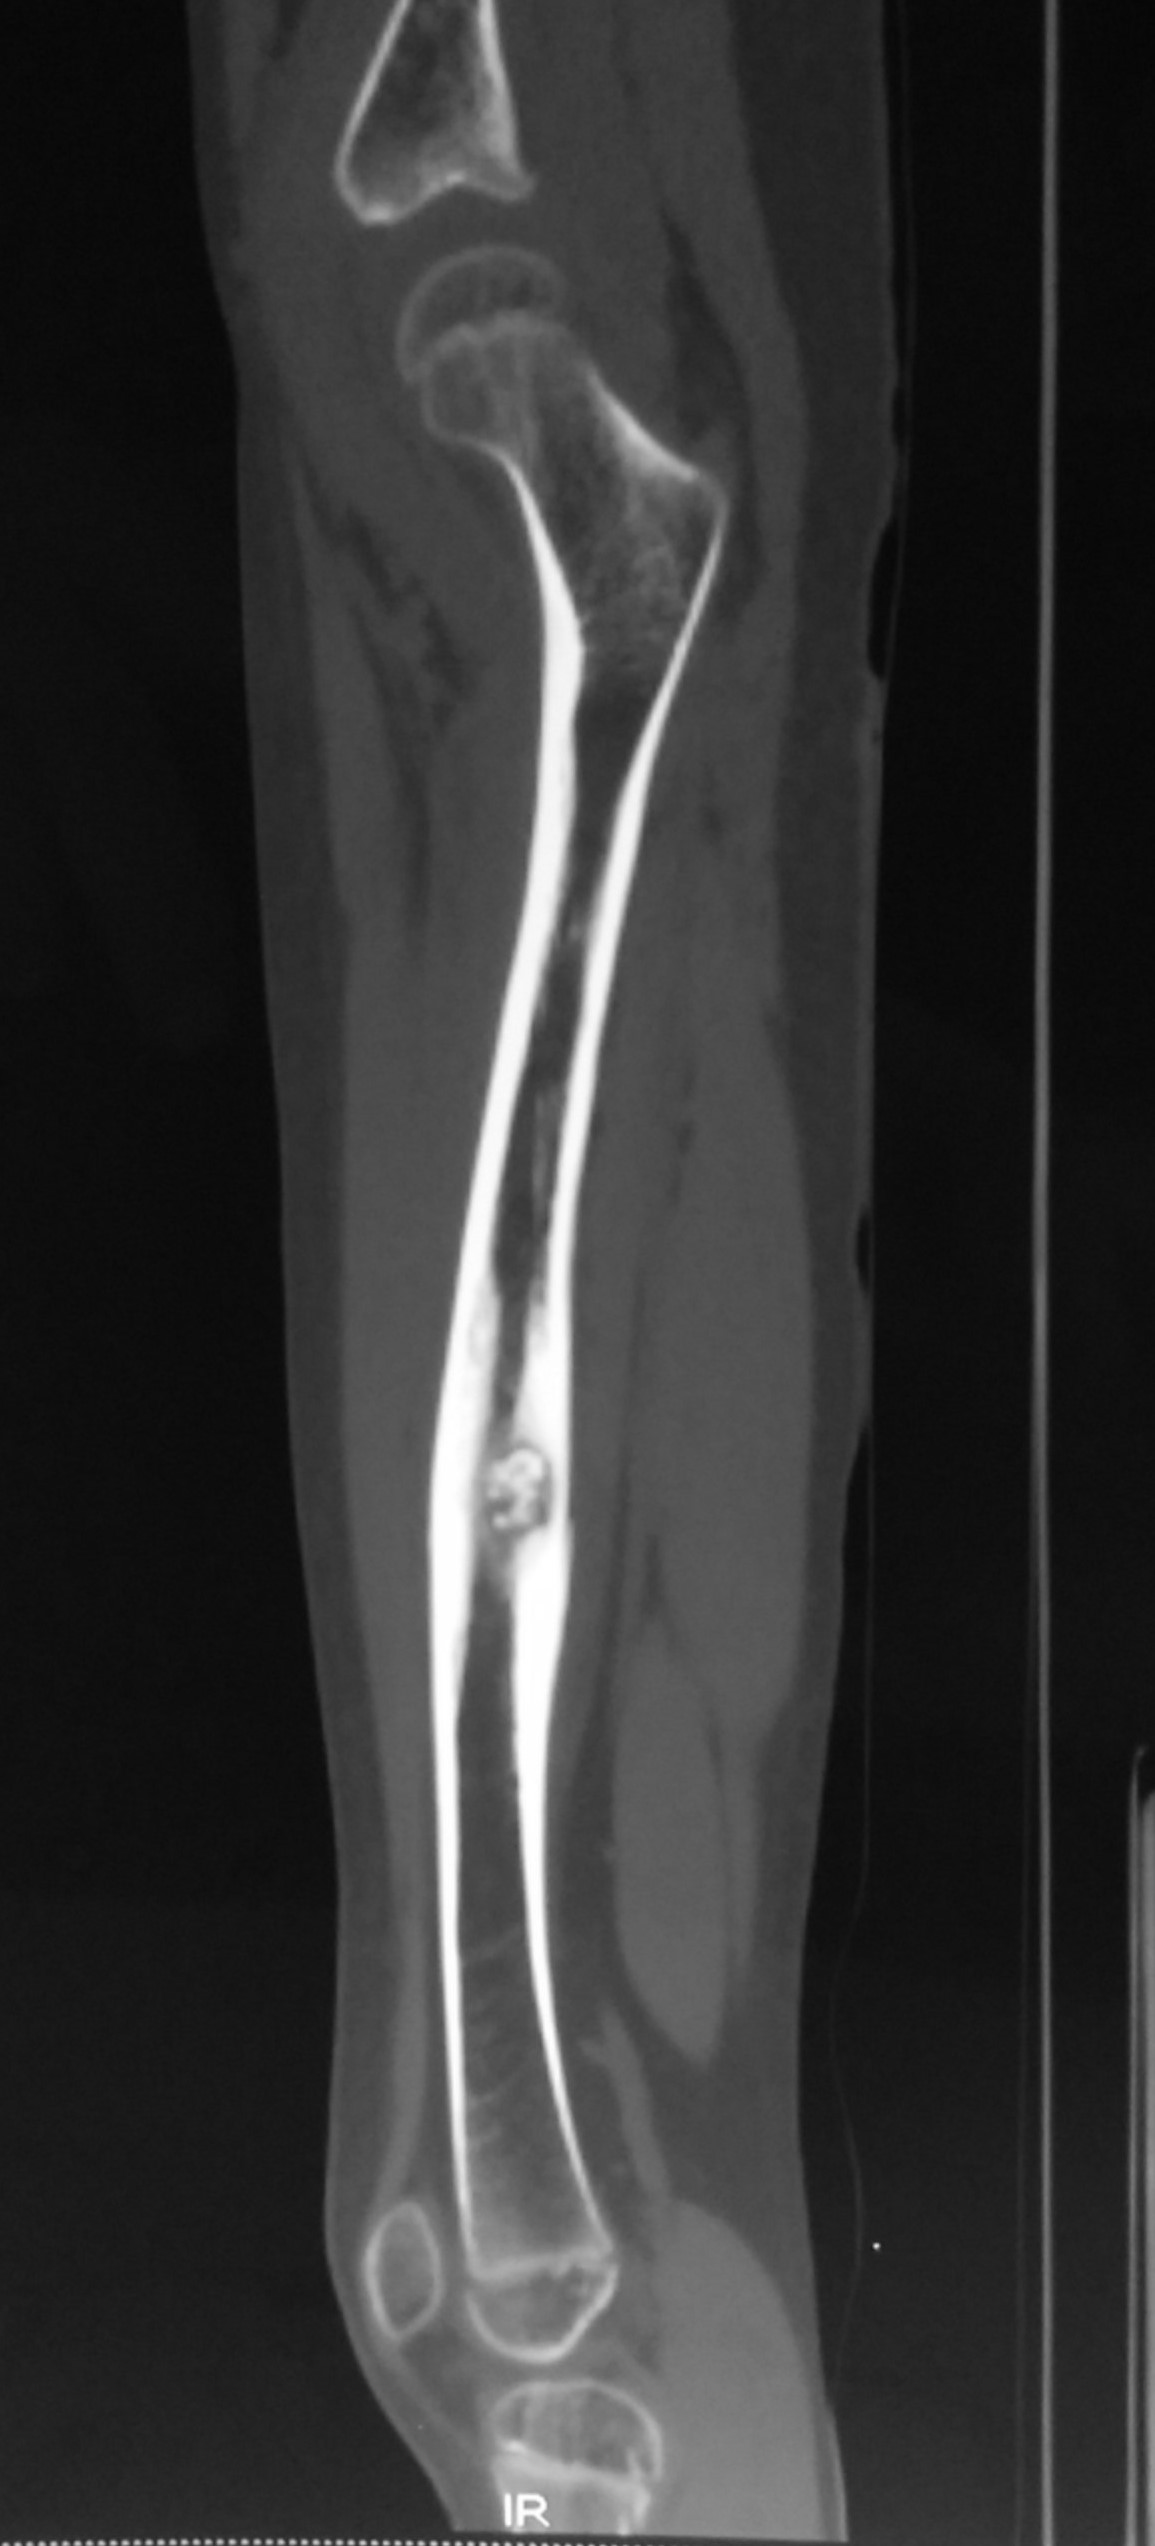

CT-scan was done to further evaluate the lesion. It confirmed the diagnosis based on the typical features.

The CT-scan also showed muscle atrophy of the left thigh muscles compared to the right thigh.